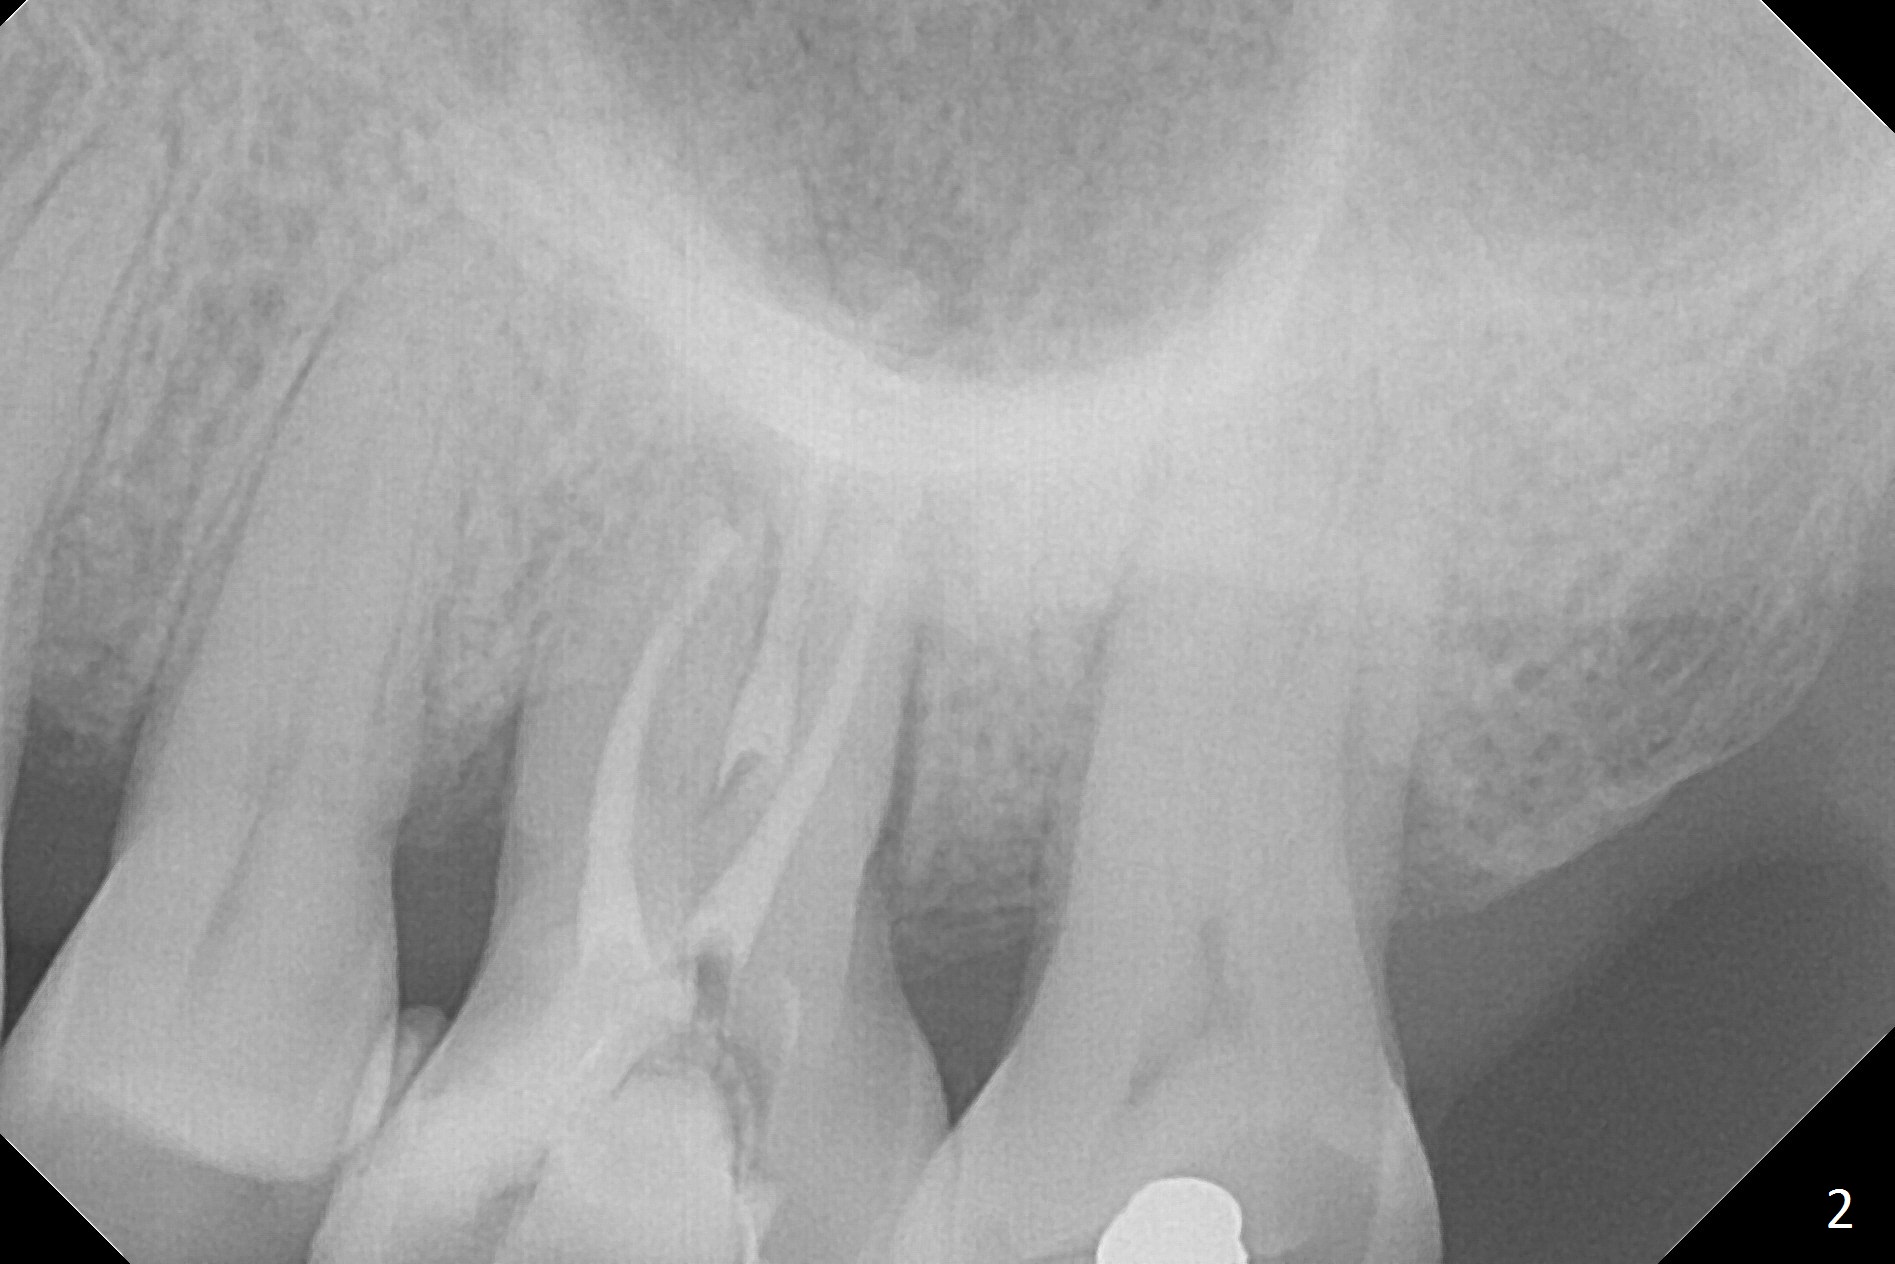

A 70-year-old woman has pain at MB root area post RCT at #14 (Fig.1,2). The tooth seems to have endo-perio disease (bone loss with gingival recession at MB) and be non-salvageable. After extraction and Metronidazole treatment, start osteotomy with 1.6 mm drill 1-2 mm shy of the sinus floor, followed by PA. Use Lindamann bur for ostetoomy position and trajectory adjustment. Use Marking Bur if necessary before Magic Drill 4.3 mm if the septum is wide. The depth of the osteotomy is 1-2 mm coronal to the sinus floor. Do not use the final drill, i.e., saving the osteotomy plug in place. Next 4.5x11 mm dummy implant is placed to push the plug upward for lifting. Place an implant as large as possible, but not violating the buccal gap (Fig.3).